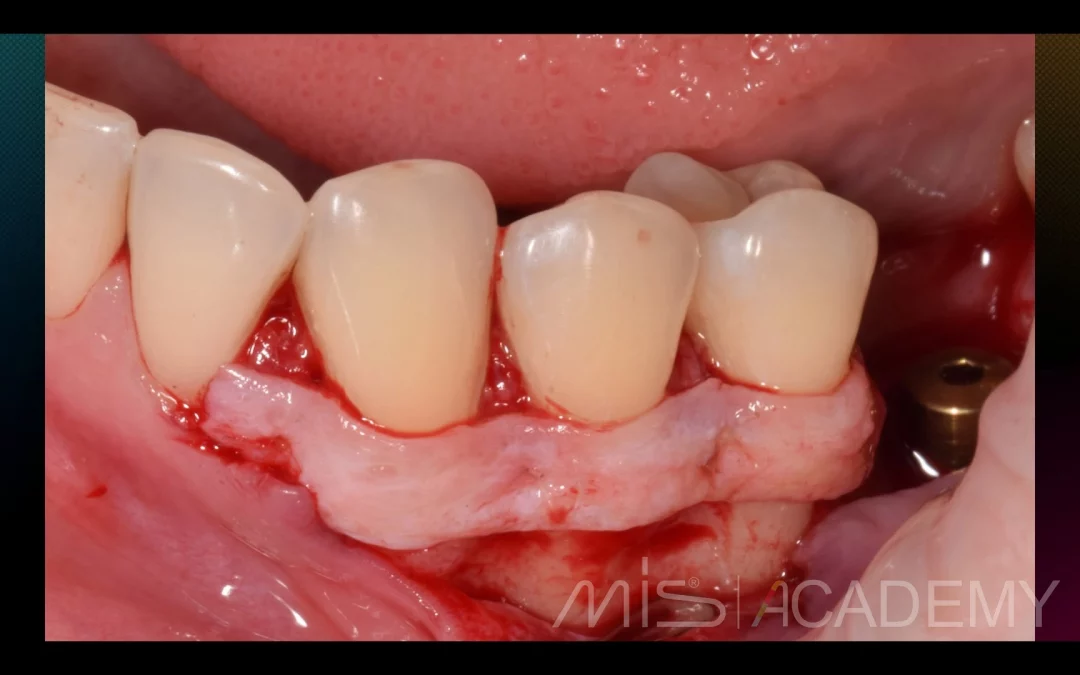

Юрий Гузеев | Клинический кейс YG-131

Восстановление объема и прикрепления. Работа с мягкими тканями в два этапа: 1 - Фиксация трансплантата к вестибулярному лоскуту. 2 - АСЛ. - Имплантаты MIS C1. - Connect. - Multi...